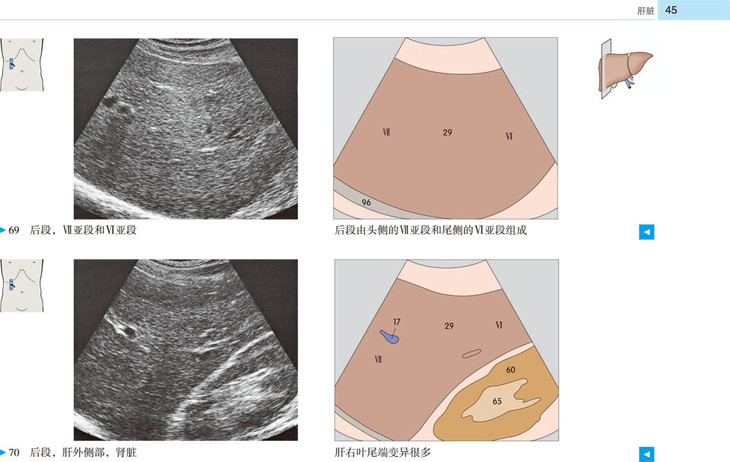

本书提供了全新的、高质量的超声图像和示意图,标示清晰、色彩丰富,为初学者带来极大的帮助。展示了腹部、盆部、甲状腺超声的所有标准切面和扫描路径,标示了各解剖结构和间隙在三维空间的解剖细节及其与超声的关系;并展示了探头定位,以及生成的截面图像、解剖结构、扫描平面在器官中的位置。本书作为优秀的初学者向导,适用于医学生、超声科医师、临床各科医师。